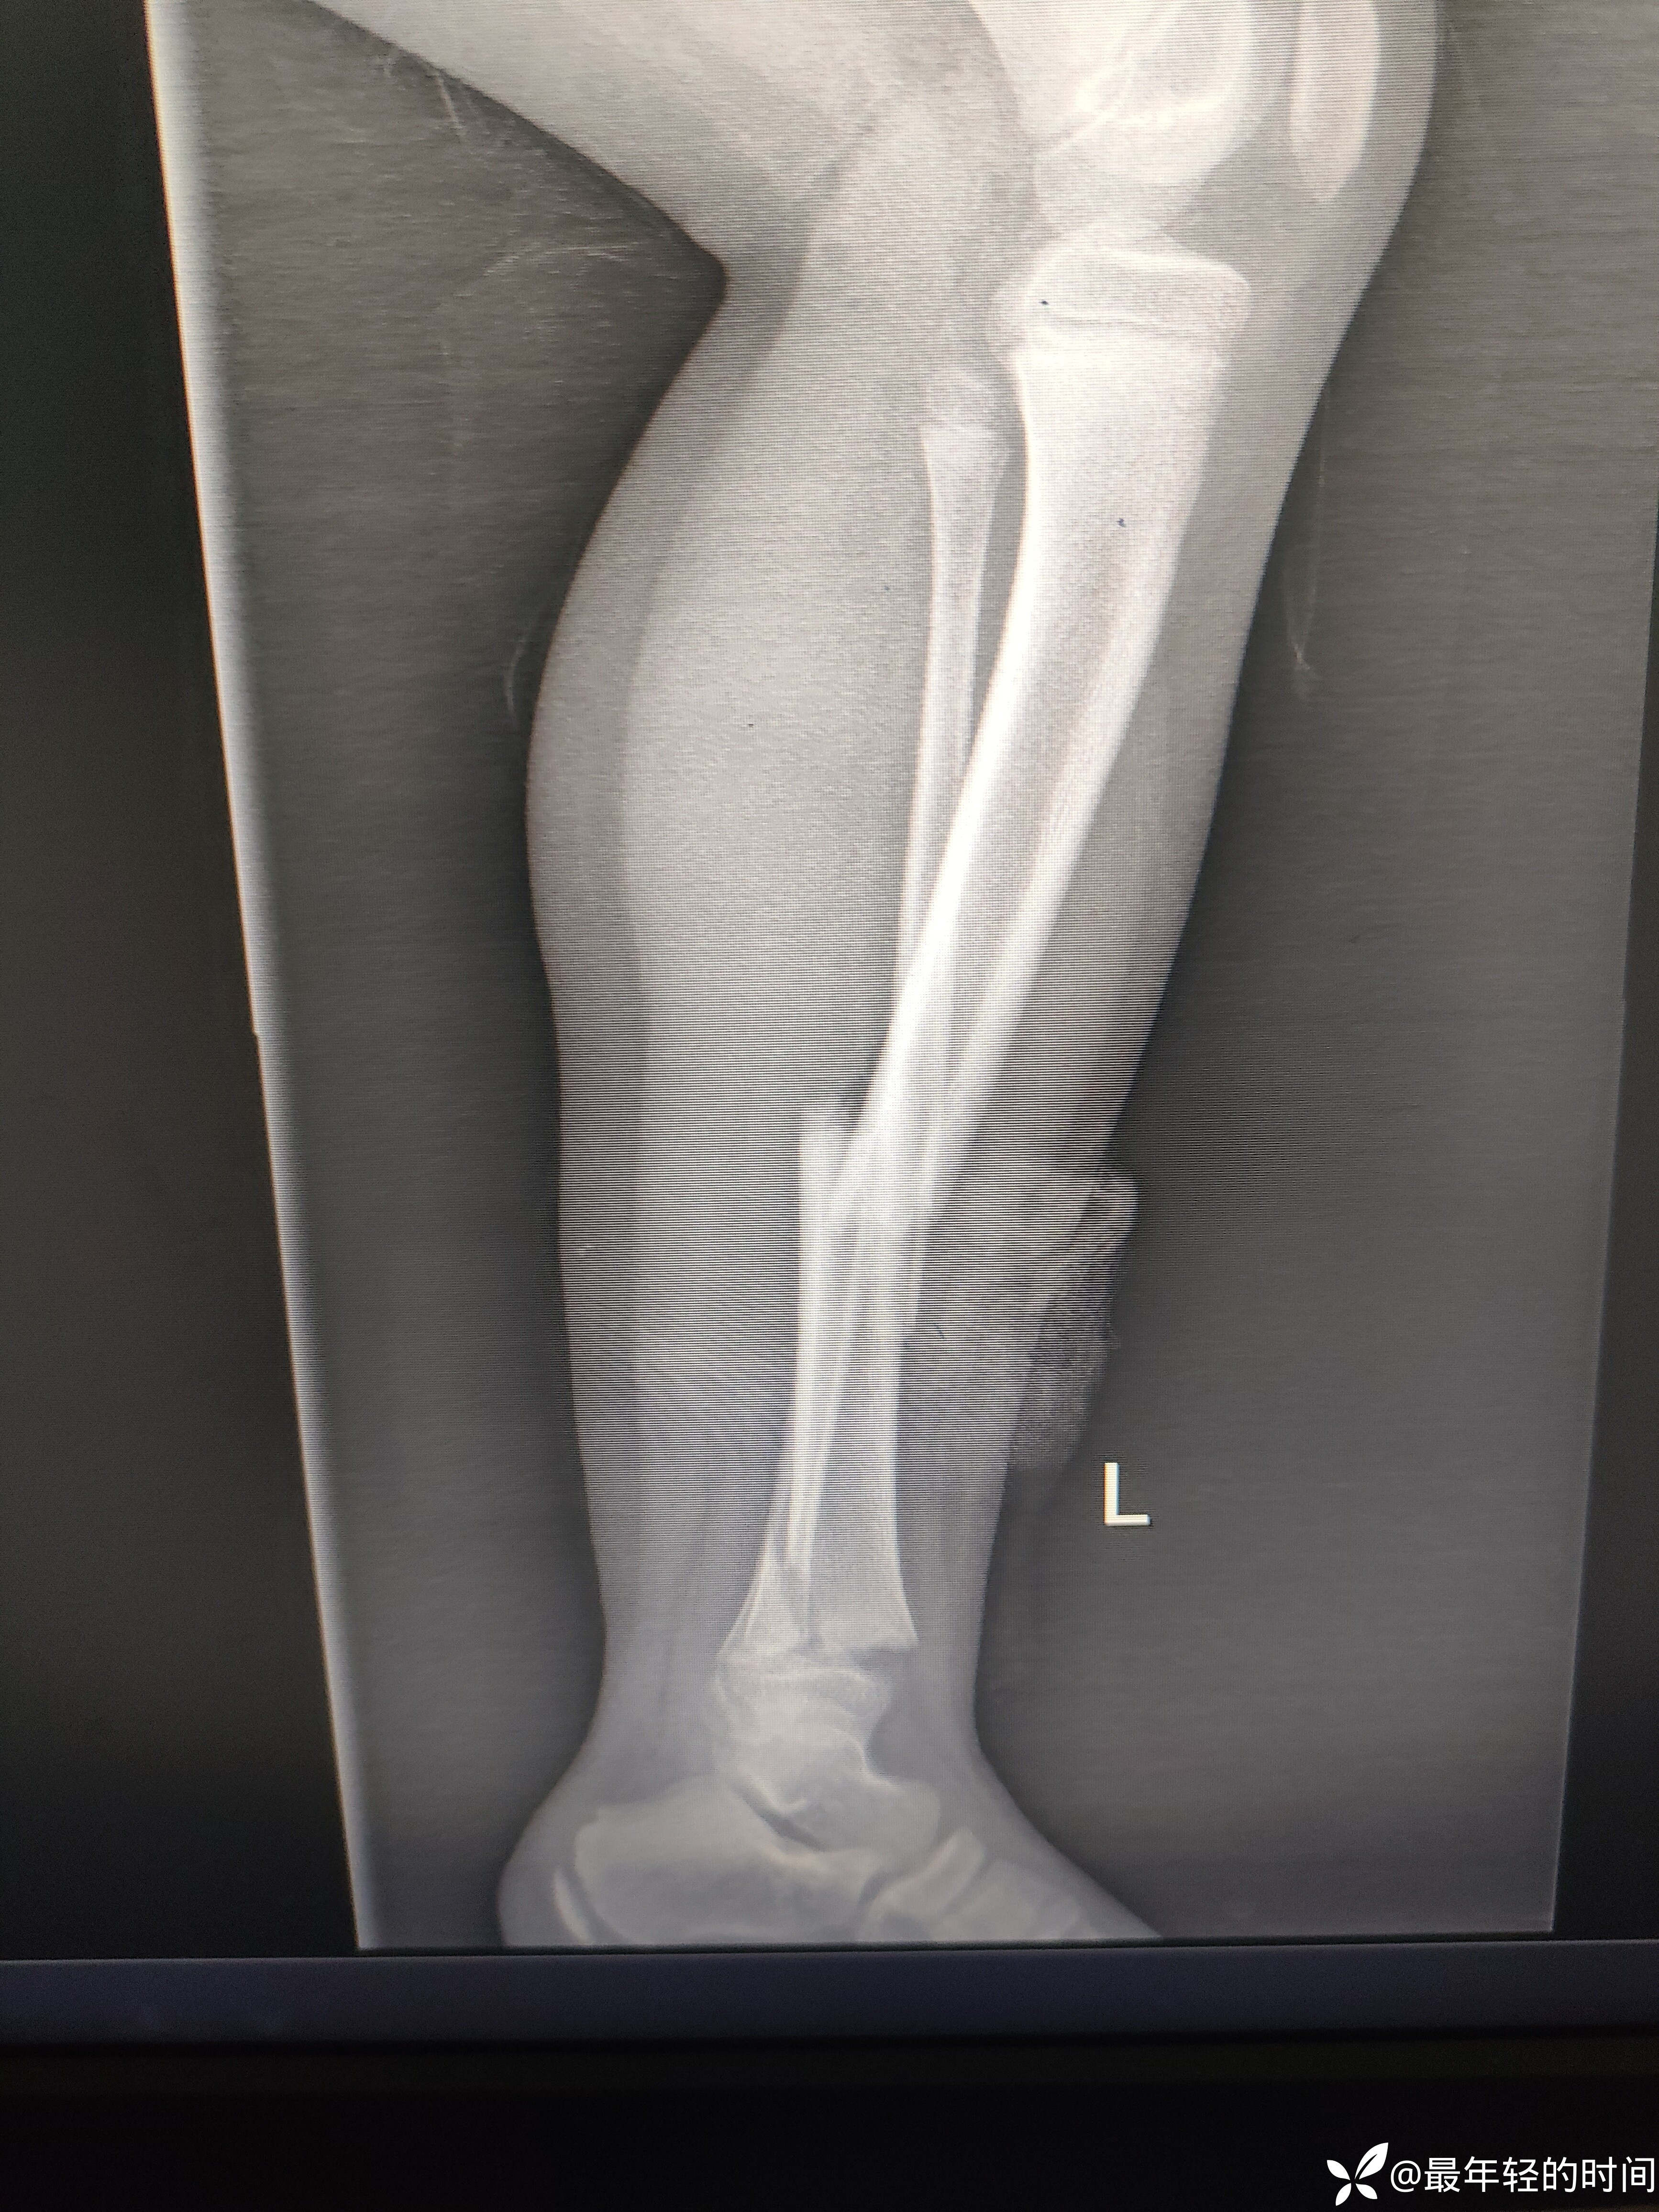

9岁儿童,男,车祸至伤。术前诊断:1.胫腓骨骨干骨折。2:胫骨骨骺损伤。3:后踝骨折。术前x线片如下: